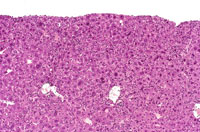

Chronic active inflammation associated with an increased incidence of hepatocellular neoplasia has been described in mice with Helicobacter hepaticus infection. The hepatitis starts as a focal, non-suppurative inflammation and progresses to chronic active hepatitis with minimal evidence of hepatocellular necrosis. Hepatocytomegaly, oval cell hyperplasia, cholangitis, bile duct hyperplasia, and cellular pleomorphism are characteristic changes associated with this infection. Helical bacterial organisms can sometimes be demonstrated with the Warthin-Starry silver stain.

Chronic active hepatitis with oval cell hyperplasia and hepatocytomegaly are characteristic of infection with Helicobacter hepaticus. In the trichrome stain, note pericellular fibrosis (right) versus the control (left).